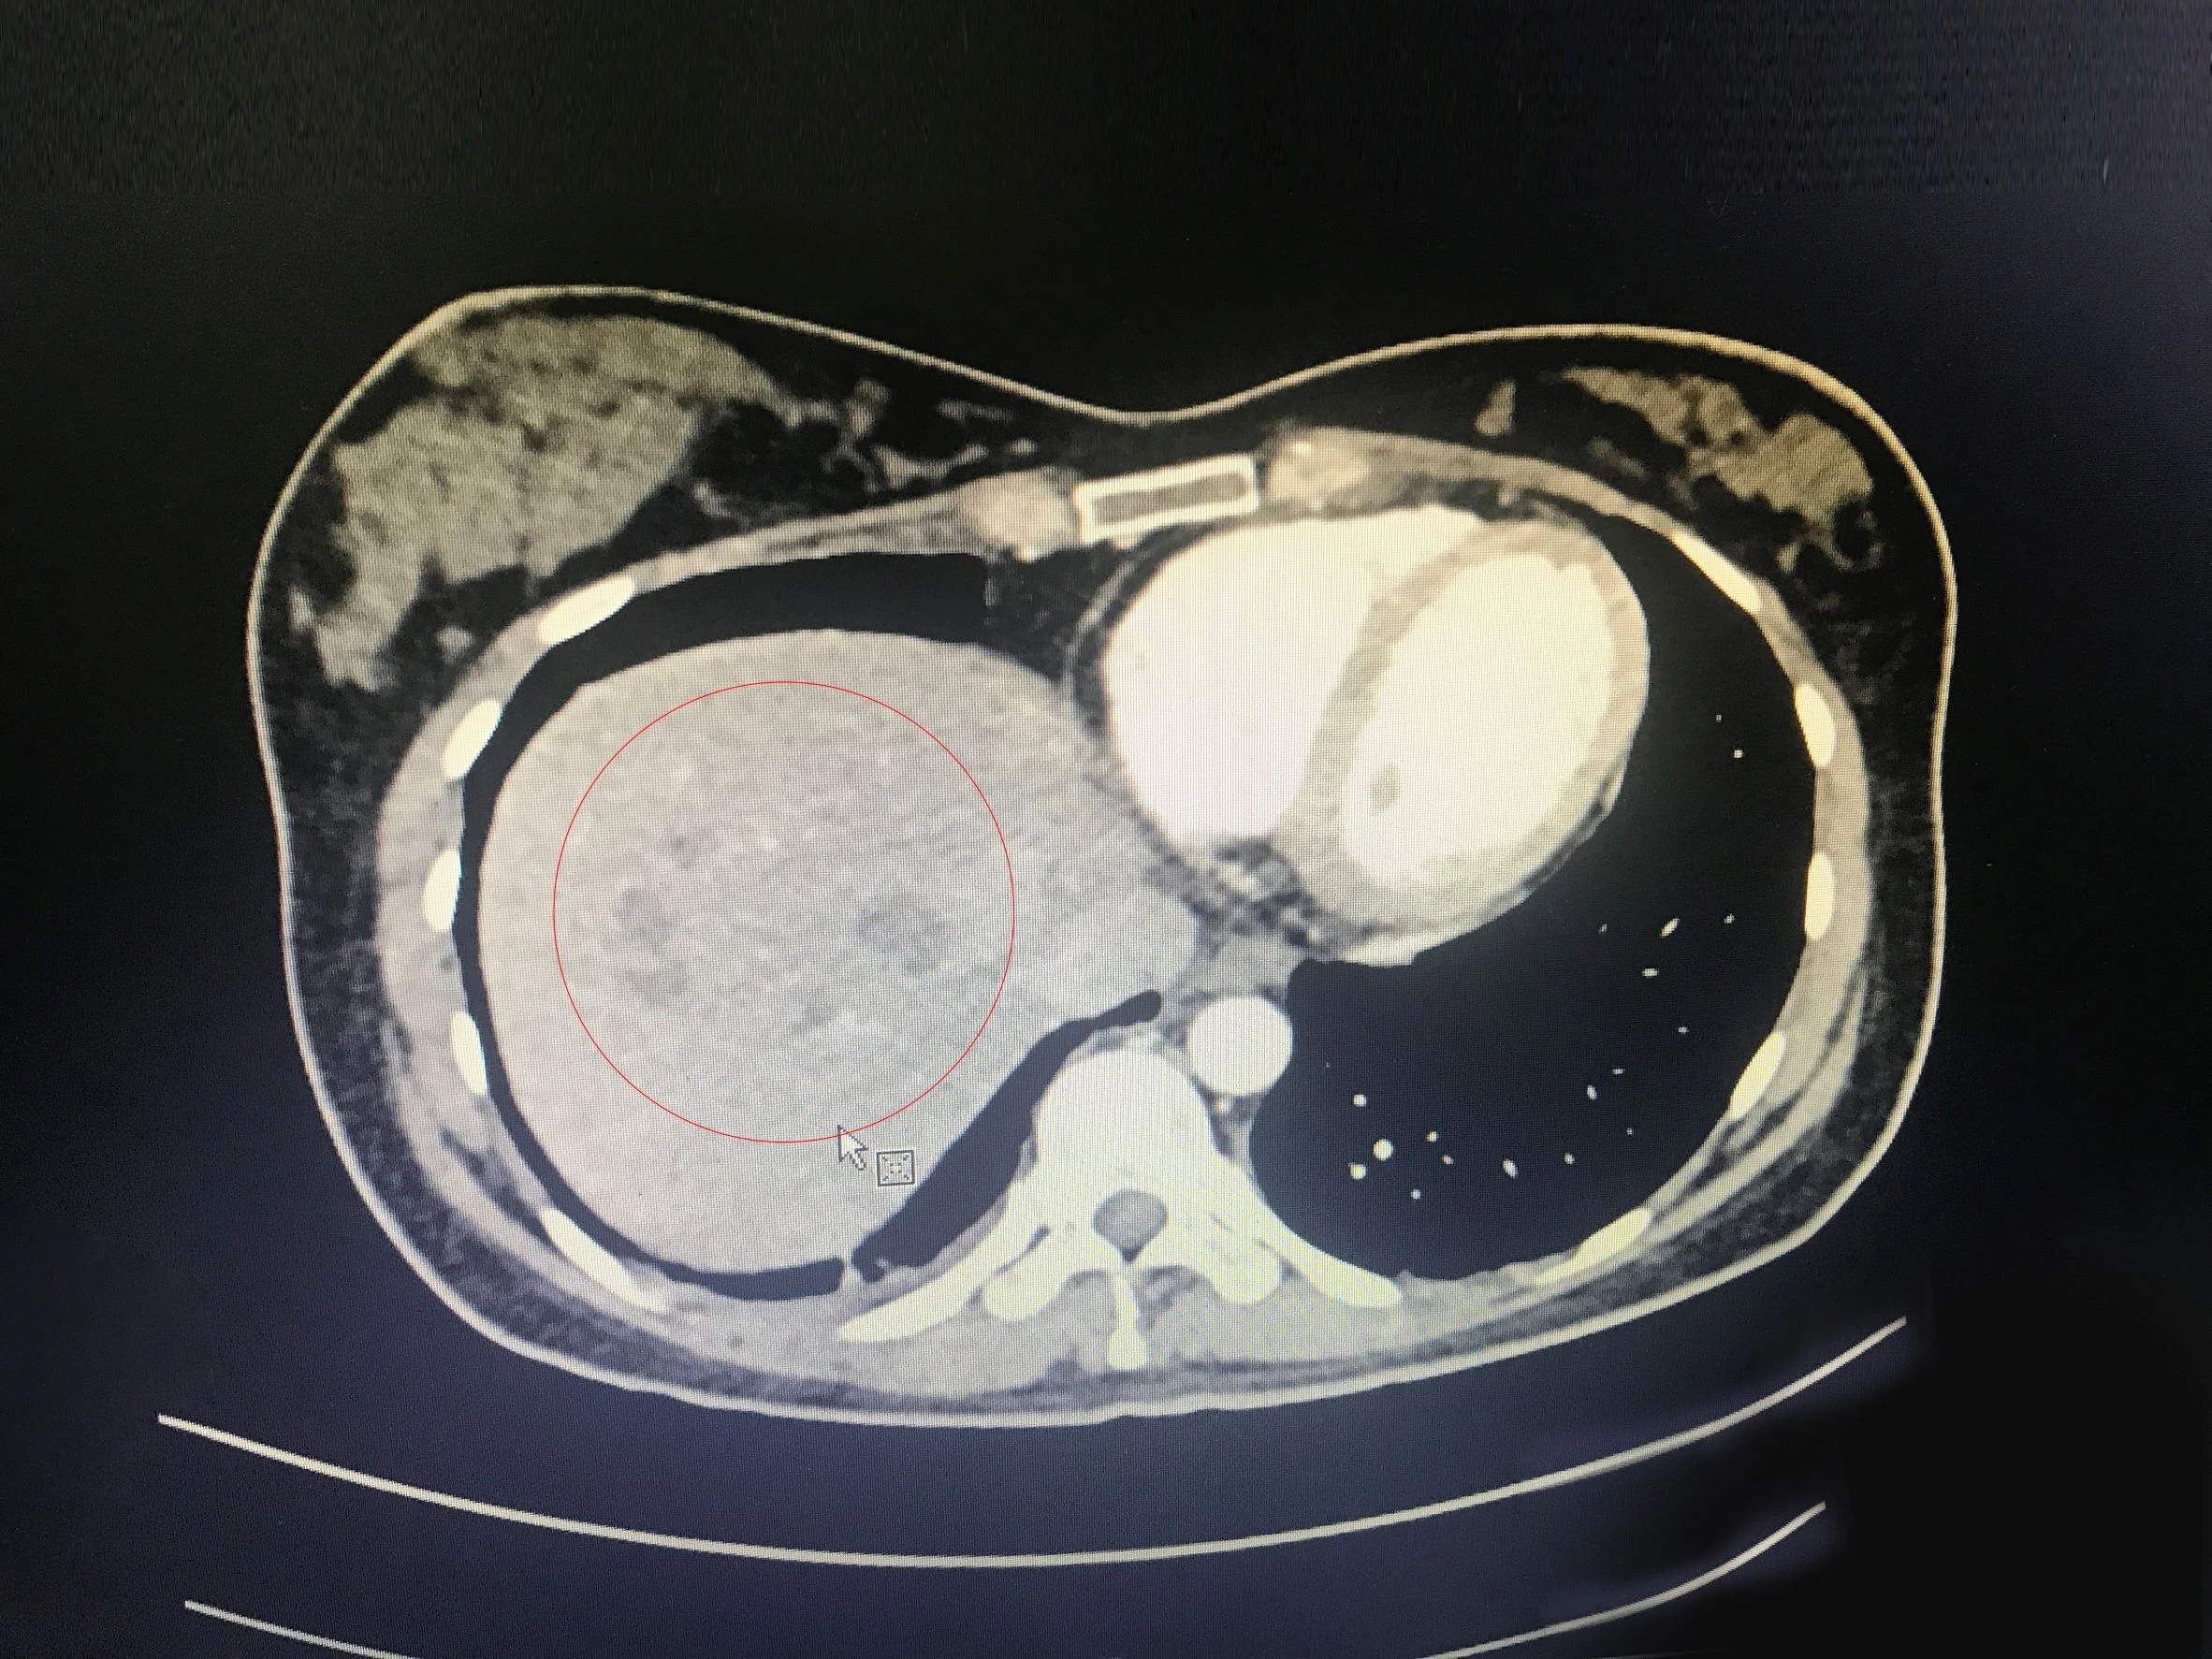

Ung thư tuyến tụy dễ gây tình trạng vàng da, mệt mỏi, khó tiêu... Các triệu chứng này thường bị bỏ qua hoặc nhầm với vấn đề khác.

Theo Hiệp hội Ung thư Mỹ, hơn 62.000 người Mỹ được chẩn đoán mắc bệnh ung thư tuyến tụy vào năm 2022, gần 50.000 người sẽ chết vì căn bệnh này.